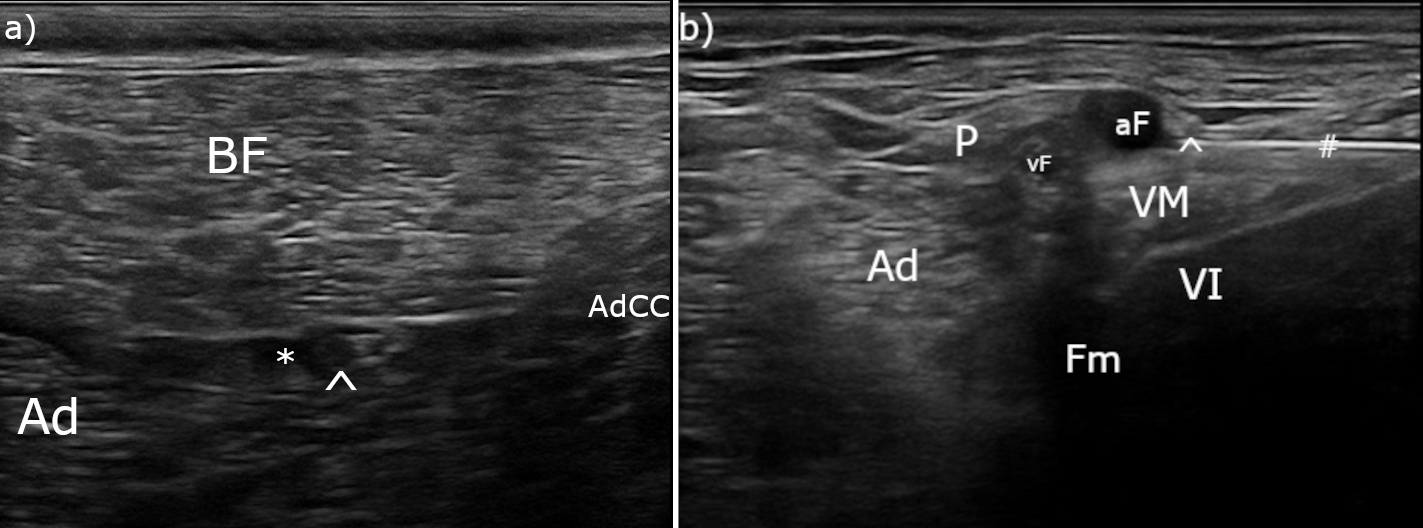

Tras rasurar y desinfectar la EPD, se realizó un bloqueo ecoguiado de los nervios ciático (Fig. 3A) y safeno (Fig. 3B) en el fémur medio,[ Portela DA, Verdier N, Otero PE: Regional anesthetic techniques for the pelvic limb and abdominal wall in small animals: A review of the literature and technique description. Vet J 2018; 238: 27-40. [PubMed] ] con bupivacaína 0,5 % (Bupivacaina 5 mg/ml, B Braun, Rubí (Barcelona), España; 0,1 ml/kg/nervio) y dexmedetomidina (1 μg/kg/nervio). Para ello se utilizó una sonda lineal multifrecuencia 3-13 MHz (MyLab Gamma, Esaote, Florencia, Italia) y agujas sonovisibles (Ultraplex® 360 x 10 mm, 30º, BBraun, Melsungen, Alemania).

(A) Imagen ecográfica del bloqueo del nervio ciático, cabeza de flecha (^): nervio ciático, asterisco (*): anestésico local depositado en la fascia intermuscular; BF: músculo bíceps femoral, Ad: músculo aductor, AdCC: músculo aductor crural caudal. (B) Imagen ecográfica del bloqueo del nervio safeno, cabeza de flecha (^): nervio safeno, almohadilla (#): aguja sonovisible, aF: arteria femoral, vF: vena femoral, P: músculo pectíneo, Ad: músculo aductor, VM: músculo vasto medial, VI: músculo vasto intermedio, Fm: fémur.

El bloqueo ecoguiado de los nervios ciático y safeno es una técnica útil y relativamente sencilla que permite impedir la transmisión del potencial de acción de los nervios (bloqueo canales del Na+), afectando a la función sensitiva y motora a partir del tercio distal del fémur. El bloqueo del ciático a nivel del fémur medio va a aportar analgesia a nivel distal a la fosa poplítea con bloqueo motor del tarso. Por otro lado, el bloqueo del nervio safeno (rama sensitiva) que se independiza del nervio femoral a nivel inguinal facilita una excelente cobertura analgésica de la cara medial del miembro posterior hasta el dedo I, pero manteniendo la función motora del cuádriceps, lo cual mejora la funcionalidad de la extremidad y el confort de los pacientes. La elección de bupivacaína 0,5 % como anestésico local persigue el objetivo de prolongar la duración del bloqueo (hasta 6-8 horas) en comparación con otros anestésicos locales como la lidocaína o la mepivacaína (2 horas).[ Duke-Novakovski T, de Vries M, Seymour C: BSAVA Manual of canine and feline anaesthesia and analgesia 3rd edition, Gloucester, British Small Animal Veterinary Association (ed), 2016. ] Además, el uso como coadyuvante de la dexmedetomidina ha demostrado prolongar aún más el efecto de la bupivacaína.[ Di Bella C, Pennasilico L, Botto R et al: Efficacy of dexmedetomidine as adjuvant to bupivacaine in femoral-sciatic nerve blocks in dogs undergoing tibial plateau levelling osteotomy (TPLO). Res Vet Sci 2023; 154: 124-131. [PubMed] ] En nuestro caso, la paciente no recuperó completamente la función motora de la extremidad hasta 36 horas tras la extubación.